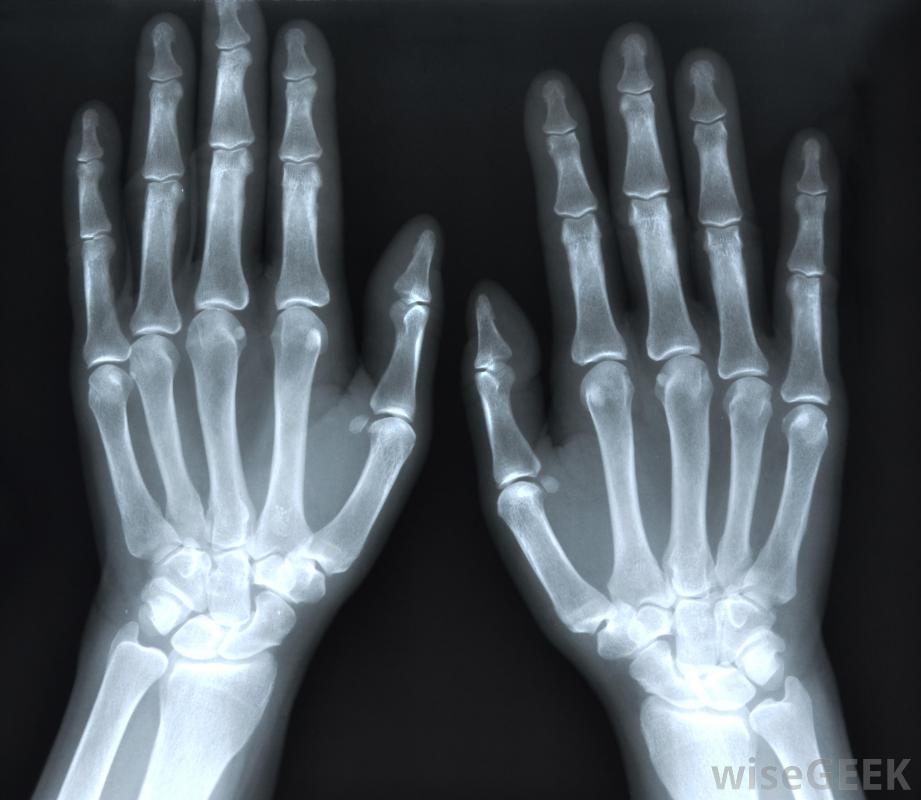

X光可能会为了诊断关节炎而服用。一些胶原缺陷是遗传性的。某些先天性疾病会干扰产生胶原的能力。许多患有遗传性结缔组织疾病的人会这样做没有产生足够的胶原蛋白,无法产生正确种类的胶原蛋白,或过度生产胶原蛋白。先天性的胶原蛋白疾病会导致结缔组织的问题,从而导致从器官损伤到肌肉矮小或虚弱等各种问题